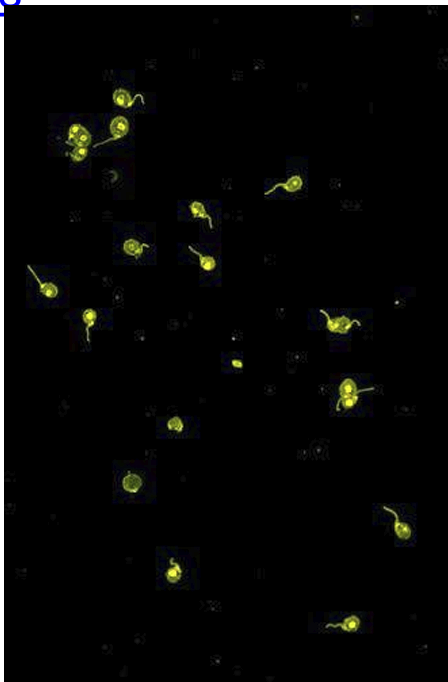

What does this show

Crithidia, kinetoplasts stain positive for anti-dsDNA Ab